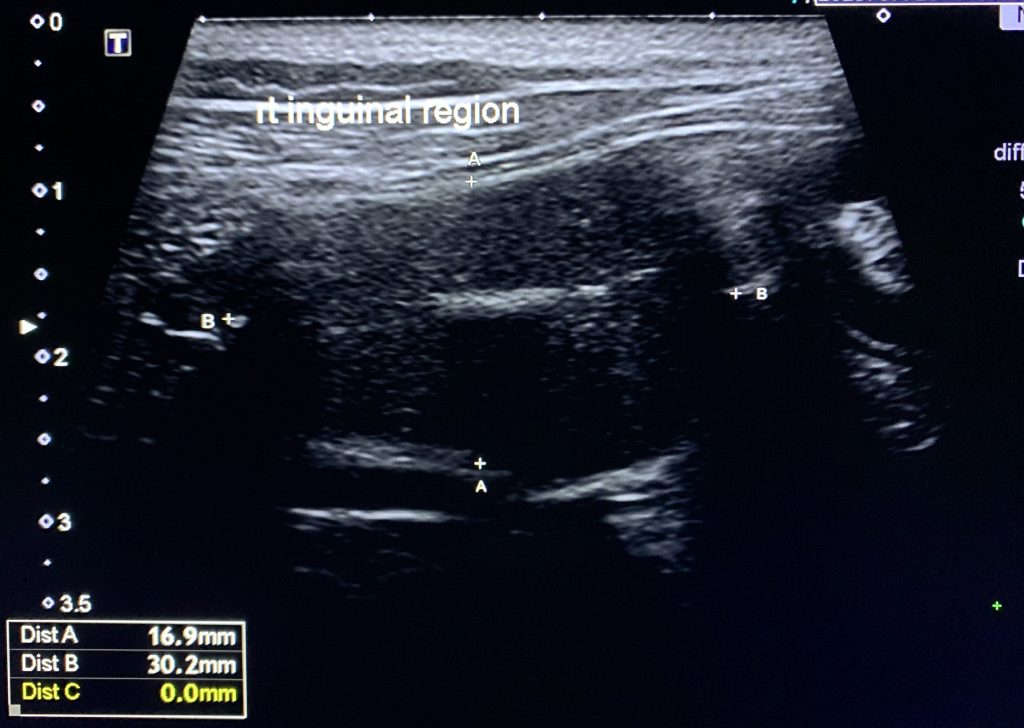

超音波下鼠蹊區域沒有發現睪丸;但在腹腔內的右腎後側,我們發現了睪丸的結構(卵圓形的球、質地均勻且粗糙、中間有一條高回音性的中膈),應該就是它了。

圖中就是小二的隱睪在超音波下的長相,透過游標可以知道這顆睪丸的長度為3公分、寬度1.5公分,比正常的睪丸小了不少。

超音波找到的左邊隱睪,和狗的隱睪一樣:卵圓形、質地均勻且粗糙、高回音性的中膈。我們在右邊也掃到另一顆。